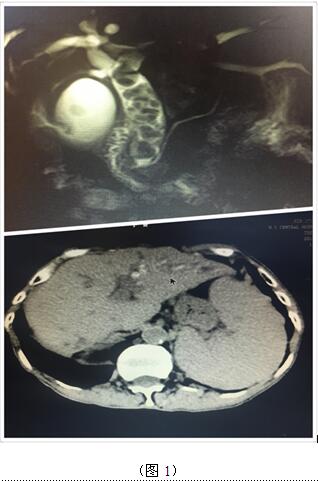

70歲高齡的曹奶奶是一個膽內(nèi)膽管結(jié)石、膽總管結(jié)石、膽囊結(jié)石的高齡患者,由于結(jié)石部位多發(fā)(圖1),當(dāng)?shù)蒯t(yī)院多次住院治療,均建議開大刀切除部分肝臟;同樣患肝臟腫瘤的張爺爺,由于腫瘤位于肝臟尾葉,而且壓迫腹腔大血管(圖2),尋遍多家醫(yī)院都只能開腹手術(shù)切除,聽說衡陽市中心醫(yī)院腹腔鏡手術(shù)技術(shù)成熟遂慕名而來。肝膽外科周玖橋主任和李鑫副主任醫(yī)師仔細(xì)分析病情后決定為倆位患者行3D腹腔鏡手術(shù)。